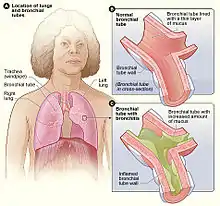

| Figure A shows the location of the lungs and bronchial tubes. Figure B is an enlarged view of a normal bronchial tube. Figure C is an enlarged view of a bronchial tube with bronchitis. | |